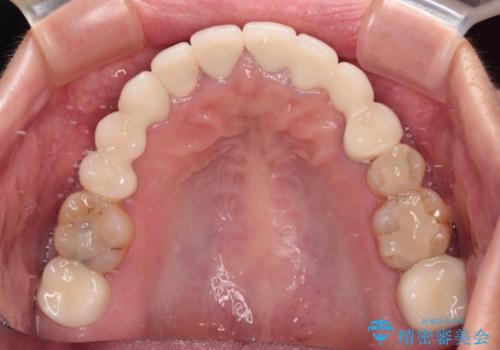

欠損やむし歯の歯をきれいなセラミックに 全顎虫歯治療

- 他院で矯正治療を終えたものの、むし歯や欠損部の治療が進められないとのことで来院された患者様です。

欠損部や、銀歯やむし歯の大きな歯はセラミッククラウンやブリッジに、小さいむし歯はセラミックインレーにて治療を行うこととしました。